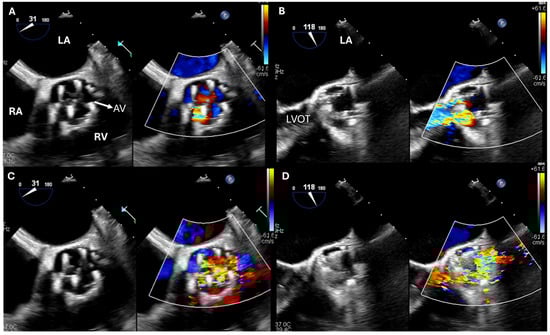

| AV repair | Describe mechanism of AR Define feasibility of repair Image coronary vessels Image ascending aorta | Ensure no/mild residual AR Exclude persistent prolapse Estimate durability of repair (measure coaptation length) |